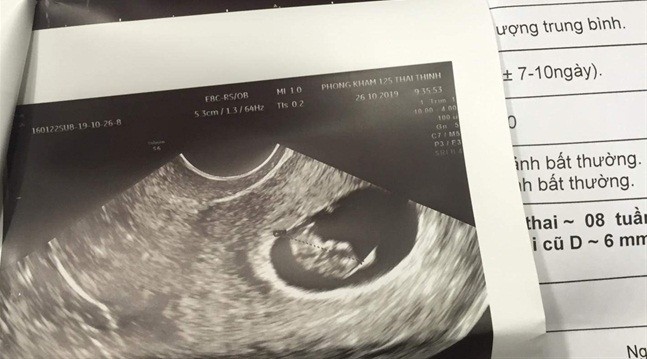

Kết quả siêu âm thể hiện chị A. đã mang thai 8 tuần tuổi

| Nạn nhân trong vụ việc là bà Đ.T.N.A. (28 tuổi, ở Hà Nội). Cuối tháng 9, bà A. vào TP.HCM hút mỡ bụng tại Thẩm mỹ viện Sophie International (Tân Định, quận 1). Vì không đủ trang thiết bị hiện đại, Thẩm mỹ viện Sophie International đã đưa bà A. sang Thẩm mỹ viện Emcas làm thủ thuật hút mỡ bụng. Một tháng sau khi hút mỡ bụng, nữ bệnh nhân phát hiện mình mang thai 8 tuần. Như vậy, vào thời điểm hút mỡ bụng, bà A. đã mang thai hơn 4 tuần. Sau khi tiếp nhận khiếu nại từ khách hàng, Thẩm mỹ viện Emcas đã nhanh chóng giải trình rằng bà A đã xác nhận với bác sĩ điều trị là không mang thai. Sau đó, Thẩm mỹ viện không xét nghiệm thai nhưng đã siêu âm bụng, khảo sát lòng tử cung cho bệnh nhân. Kết quả siêu âm không thấy túi thai nên đã thực hiện phẫu thuật hút mỡ bụng cho bệnh nhân. Trong khi đó, phía Thẩm mỹ viện Sophie International đã cho rằng sau khi phát hiện vấn đề, Thẩm mỹ viện và bệnh nhân đã thảo luận về các giải quyết và thỏa thuận. Bệnh nhân yêu cầu Thẩm mỹ viện Sophie International bồi thường 1 tỷ đồng với lý do chi trả chi phí thuốc và giải quyết sự việc. Nhận thấy đây là điều vô lý nên Thẩm mỹ viện Sophie International không đồng ý. Ngày 2/11, bà Nguyễn Thị Huỳnh Mai - Chánh văn phòng Sở Y tế TP.HCM - cho biết ngay sau khi tiếp nhận thông tin về vụ việc trên, đơn vị đã kiểm tra Thẩm mỹ viện Sophie International. Tại thời điểm kiểm tra, Sở Y tế TP.HCM phát hiện Thẩm mỹ viện Sophie International chưa được cấp phép nhưng đã tư vấn cho khách hàng có nhu cầu hút mỡ bụng. Hiện Sở Y tế đã ra quyết định đình chỉ hoạt động đối với Thẩm mỹ viện này. |